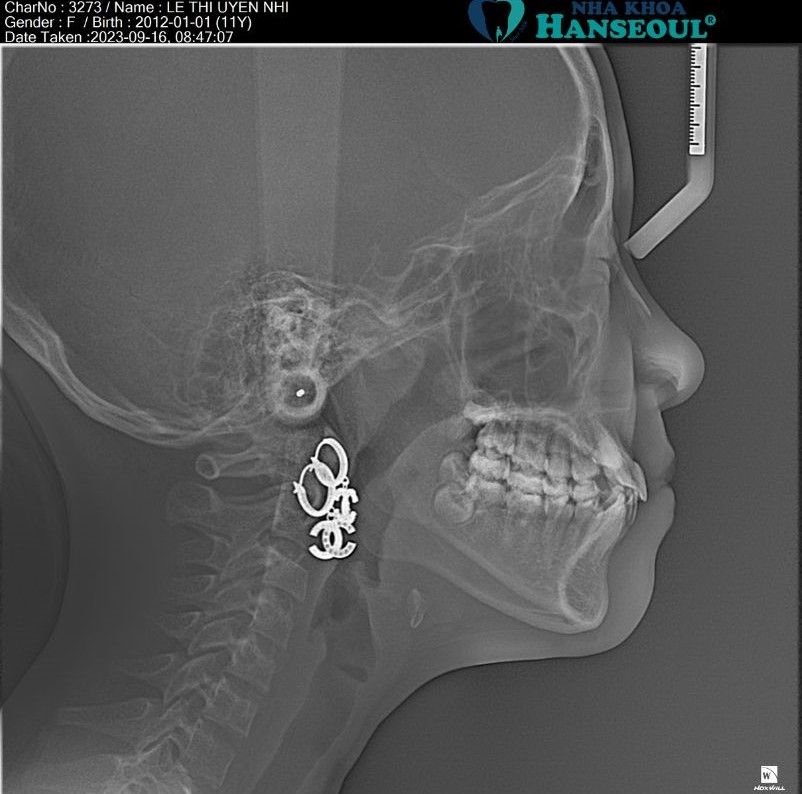

Tình trạng được xác định thông qua:

- Khám lâm sàng (ngoài mặt và trong miệng)

- Phim X-quang toàn cảnh (Panoramic) đánh giá răng vĩnh viễn và cấu trúc xương hàm